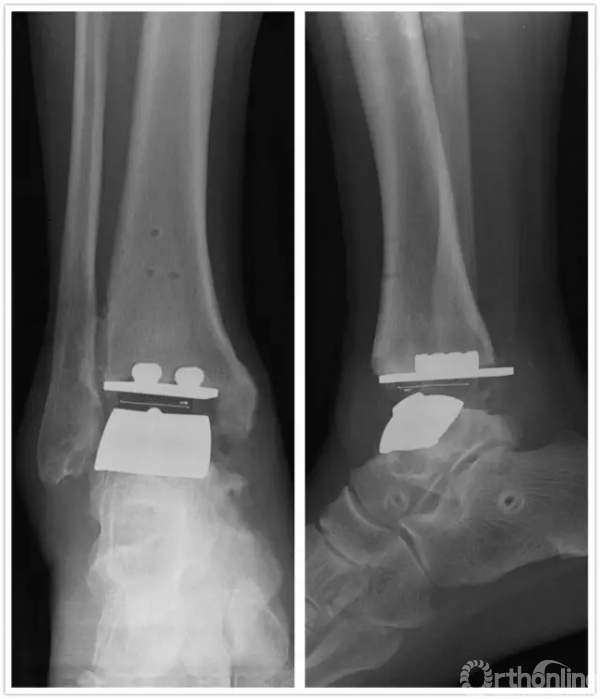

手术中首先沿原手术切口进入,保护神经血管肌腱组织,清理踝关节假体周围骨赘,取出原关节假体,将患足置于专门的定制支架中,在透视下反复调整足踝及导针位置,力求最高精确度。在导板的定位下进行胫骨远端和距骨截骨,试样假体大小,置入合适匹配的踝关节假体及垫片完成全踝关节假体的置换,然后再行距下关节融合术。历经4小时,手术过程非常顺利,术后患者恢复良好,手术取得圆满成功。